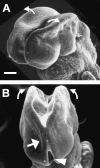

Cranial neurulation is the embryonic process responsible for formation of the brain primordium. In the mouse embryo, cranial neurulation is a piecemeal process with several initiation sites and two neuropores. Variation in the pattern of cranial neurulation occurs in different mouse strains, and a simpler version of this morphogenetic scheme has been described in human embryos. Exencephaly is more common in females than in males, an unexplained phenomenon seen in both mice and humans. As the cranial neural tube closes, a critical morphogenetic event is the formation of dorsolateral bending points near the neural fold tips, which enables subsequent midline fusion of the neural folds. Many mutant and gene-targeted mouse strains develop cranial neural tube defects, and analysis of the underlying molecular defects identifies several requirements for normal dorsolateral bending. These include a functional actin cytoskeleton, emigration of the cranial neural crest, spatio-temporally regulated apoptosis, and a balance between cell proliferation and the onset of neuronal differentiation. A small number of mouse mutants exhibit craniorachischisis, a combined brain and spine neurulation defect. Recent studies show that disturbance of a single molecular signalling cascade, the planar cell polarity pathway, is implicated in mutants with this defect.